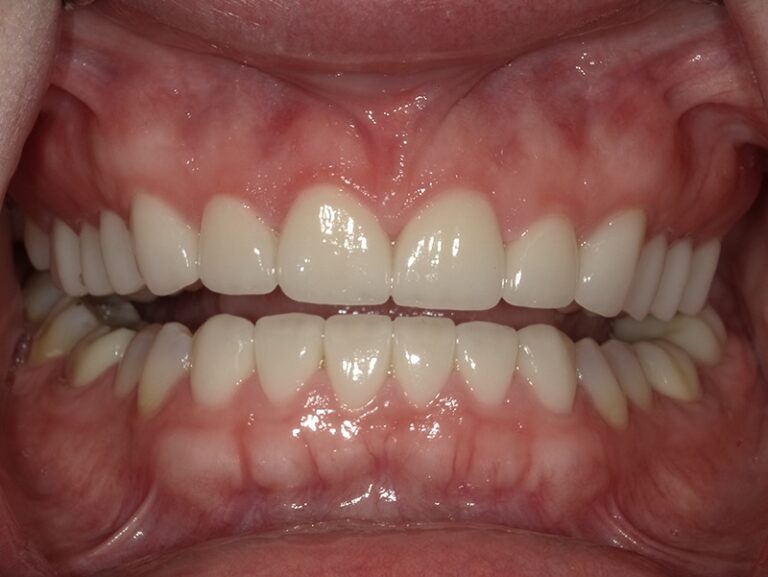

We began this patient's cosmetic journey with SureSmile clear aligners. We were able to accommodate patient's request of a shorter aligner treatment length, and move on to porcelain restorations. We placed 12 upper crowns and 6 lower veneers, thus giving her a beautiful new smile in a shorter timeframe!